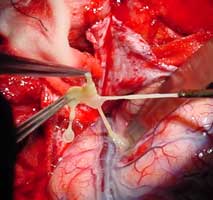

2、皮質部囊蟲引起癲癇局限性發作、腦室內囊蟲出現阻塞症狀者,應手術摘除囊蟲。

3、腦底葡萄狀蟲體造成交通性腦積水者,可手術摘除蟲體。

手術摘除囊腫